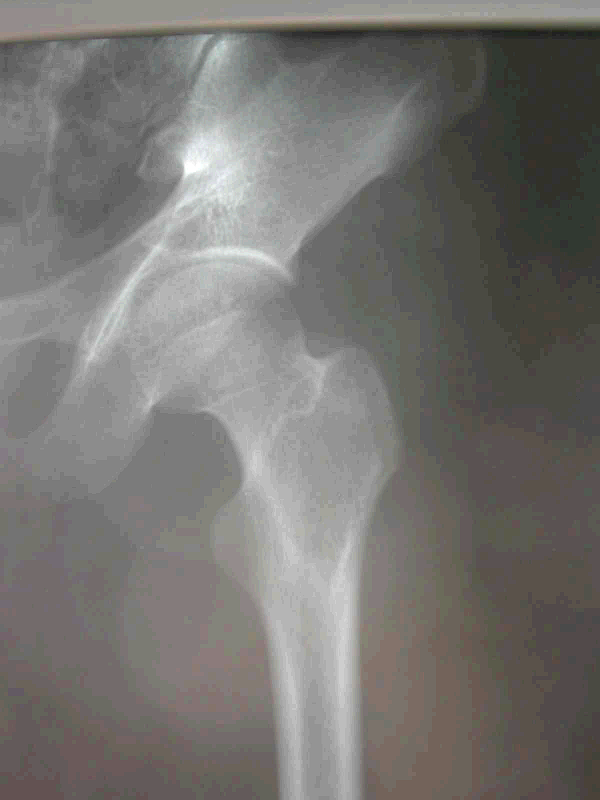

2.病例2:男 65岁 右股骨头颈部透明细胞软骨肉瘤

图 9 术前X片